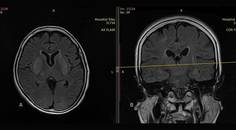

Case Report: Noninvasive Intracranial Pressure Monitoring

Ankit Bansal, MD; Neetika RastogiAnkit Bansal, MD; Neetika Rastogi